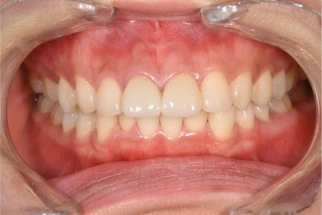

前歯2本のセラミック治療 症例①

前歯2本のセラミック治療 症例

治療例

前歯2本のセラミック治療 症例②

前歯2本のセラミック治療 症例③

費用例

総額 198,000円(税込)

年齢

20代女性

主訴

前歯が気になる

治療期間

1ヶ月

施術(治療)内容

前歯2本のセラミック治療

リスク・副作用

費用がかかる

麻酔費用

22,000円×2回=44,000円

治療費用

154,000円(税込)